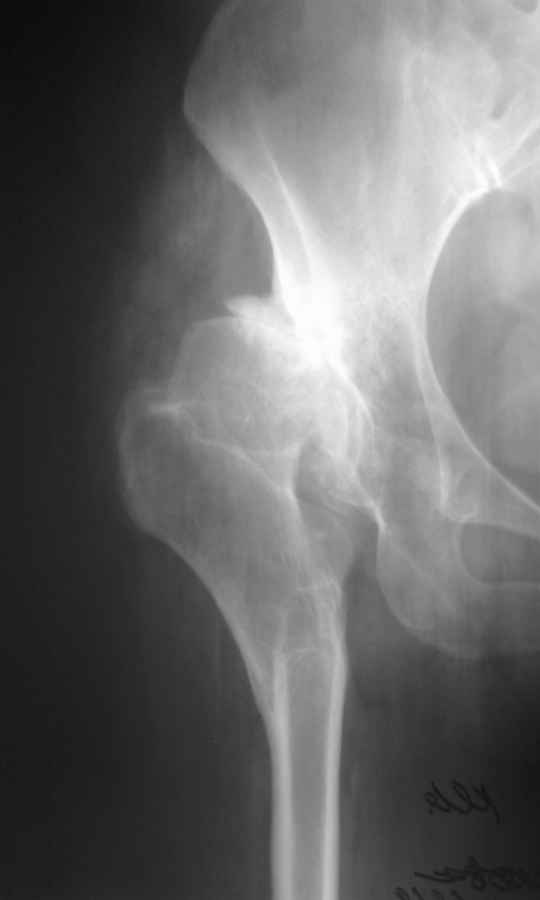

Уважаемый Андрей, ситуация не простая, нет обзорной Р-графии таза, поэтому сложно провести правильное планирование операции. Тем не менее, при планировании операции вертлужный компонент я бы установил в анатомическое положение. В отношении ножки - может быть два решения. Мое предпочтение - (операция типа Paavilaanen'a) поперечная остеотомия бедра на уровне чуть выше деформации, установка ножки Вагнера, скорее всего 190 мм, хотя возможно удастся обойтись и конической ножкой, это зависит от необходимой компенсации длины ноги. Продольная остеотомия б/вертела с последующей фиксацией к диафизу бедра с натяжением мышц. Есть и другой вариант - укорачивающая остеотомия в зоне деформации бедра с установкой ножки со стороны шейки. Мы делали и то и другое, первый вариант проще. В этой операции есть масса нюансов и нужно иметь опыт операций при дисплазии ТБС.

Был у нас подобный случай

Выполнена одномоментная коррекция деформации, эндопротезирование DePyu Pinnacle-AML. Пластинка с деротационной целью. При использовании ножки с прямоугольным сечением, думаю, можно и без нее.

Уважаемый Андрей! Действительно сложно спланировать операцию без обзорного снимка таза, а так же рентгенограмы бедра в аксиальной проекции. По поводу реконструкции бедренной кости могу предложить следующие варианты опробированные на практике (если есть необходимость пришлю Р-граммы).

-Клиновидная остеотомия бедра на вершине деформации, с углом открыты внутрь. Это позволит выпрямить бедро, добиться полной адаптации обоих фрагментов. Использование ножки Вагнера не позволит фиксировать проксимальный отломок и потребуется какая то дополнительная фиксация, возможно пластиной.

-То же самое с использованием ножки Helios (Biomed) позволит выполнить вполне качественный остеосинтез (ножка из двух частей и позволяет оптиально зафиксировать оба фрагмента), к тому же с возможностью блокирования. Поэтому дополнительной фиксации не потребуется.

В прищепке случай 1999 года - эндопротезирование после операции Шанца-Илизарова. Возраст пациентки 45. Коррекция была в 17 лет. А Рыков Хабаровск.